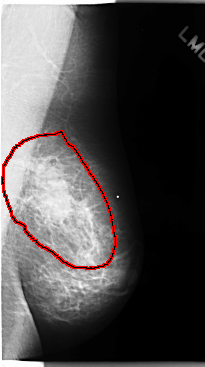

C_0108_1.LEFT_CC

LEFT_CC LINES 4744 PIXELS_PER_LINE 2560 BITS_PER_PIXEL 12 RESOLUTION 50 OVERLAY

FILE: C_0108_1.LEFT_CC.OVERLAY

TOTAL_ABNORMALITIES 1

ABNORMALITY 1

LESION_TYPE MASS SHAPE IRREGULAR MARGINS ILL_DEFINED

ASSESSMENT 5

SUBTLETY 5

PATHOLOGY MALIGNANT

TOTAL_OUTLINES 1

BOUNDARY